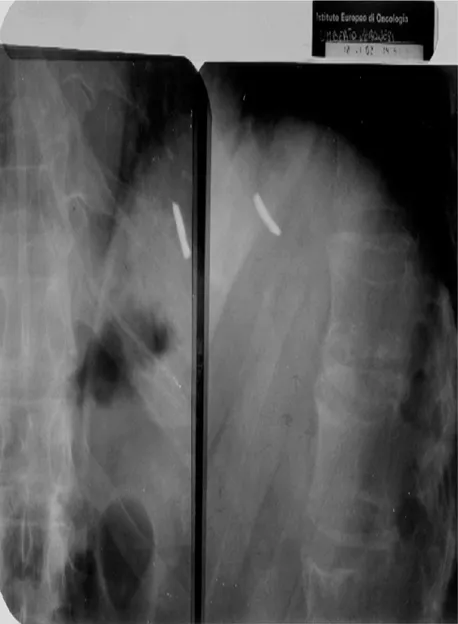

Foto 1. Radiografia del costato di Veronesi. È ben visibile la scheggia di cui fu impossibile l’estrazione perché troppo vicina al cuore. Il Professore porta sempre con sé questa lastra per passare i controlli di sicurezza dei metal detector.